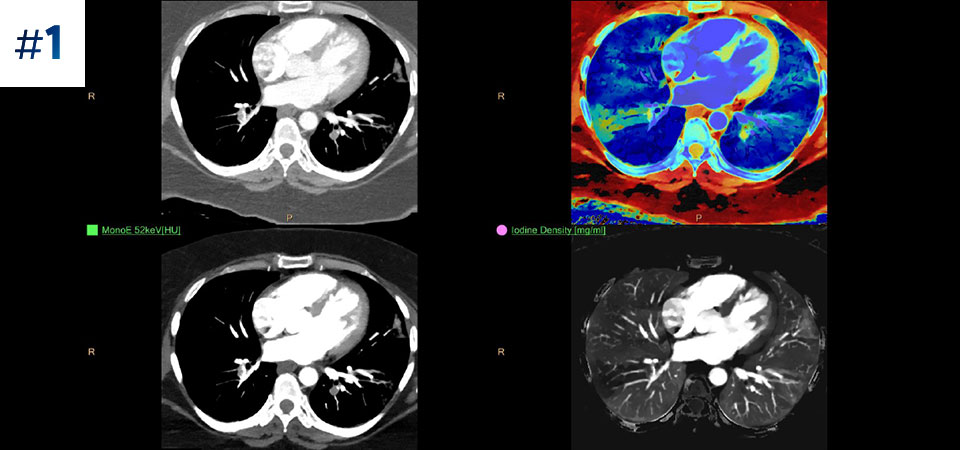

With detector-based spectral, you acquire multiple layers of data—conventional and spectral—within a single exposure and without special scan modes for improved tissue characterization and visualization.

Scan as usual A single scan for fast, low-dose conventional and spectral data for every patient, every time.

Always available 100% spectral, 100% of the time for results that are always available on-demand, even retrospectively.

Reduced follow-up exams Improved tissue characterization and visualization may reduce the need for follow-up scanning for sub-optimal exams and incidental findings.

Can you solve the mystery diagnosis using spectral?

Go beyond conventional CT. See how layers of spectral-detector results can enhance your diagnostic confidence.